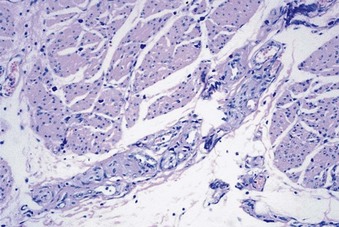

In a study looking for active immune cellular deposition in BPS/IC patients, no statistically significant difference between controls and nonulcerative IC patients was identified (Harrington et al, 1990). In contrast, the ulcerative BPS group had focal sheets of plasma cells, aggregates of T cells, B-cell nodules, a decreased or normal helper-to-suppressor cell ratio, and suppressor cytotoxic cells in germinal centers. Flow cytometry analysis of peripheral blood lymphocyte subsets showed increased numbers of secretory-Ig–positive B cells and activated lymphocytes in the nonulcerative group and increased numbers of secretory-Ig–positive cells and activated lymphocytes in the ulcerative group. These results may suggest a partial role for an immune mechanism in IC. Erickson and coworkers (1997a) have also noted a major difference in inflammatory cell types as well as clinical features in BPS/IC patients with severe inflammation, suggesting two different patient groups with two different underlying pathophysiologies.

Hanno and colleagues (1990) found CD4 cell predominance in all layers of the bladder in BPS/IC patients. Christmas (1994) reported increased numbers of CD4+ and CD8+ T cells in bladder biopsy specimens from patients with IC and bacterial cystitis as compared with controls. These T cells were present in the urothelium and submucosa but not in the detrusor. Control bladder tissue demonstrated only CD8 cells in the urothelium and both CD4+ and CD8+ cells in the submucosa. The number of plasma cells was significantly greater in IC patients than in normal controls and controls with bacterial cystitis.